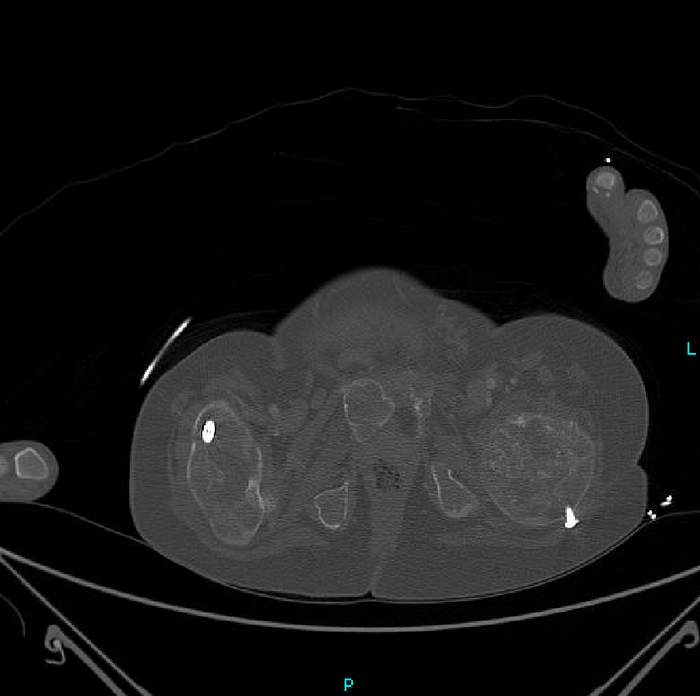

Но вернёмся к случаю: Пациент - девочка, 15 лет. Поступила после ДТП. У нас было проведено КТ-обследование по протоколу политравмы (голова / шея / грудь / живот / таз), где свежих переломов обнаружено не было, но были непонятные леденцы с костями, а именно структура и форма костей со следами старых переломов (грудная клетка и таз с бедренными костями) и, как следствие, их деформацией + следы проведённого остеосинтеза (операция с последующей фиксацией кости тем или иным способом) обоих бедренных костей. Сегодня без пометок / стрелочек, так как картинки говорят сами за себя (всё в костном окне, и всё, что мы видим - кости):

Структура костей напоминала таковую при фиброзной дисплазии (аномалия развития костной ткани с замещением нормальной кости фиброзной тканью, не является опухолью), но, обычно, эти диcплазии возникают в одном месте, т.е. поражают 1 кость (моностотическая форма) и, намного реже, бывают множественные поражения (полистотическая форма), но не всего скелета, как в нашем случае.